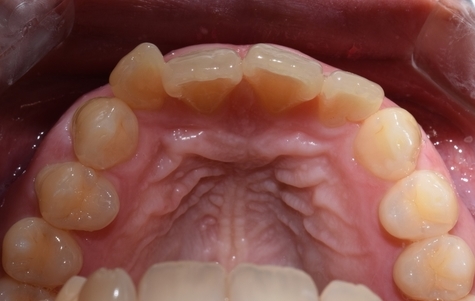

이번에도 환자분이 사진 공개에 동의한 케이스입니다.

치아가 고르지 못한 상태였고

처음 상담시 교정을 추천드렸으나

환자분께서 최대한 빠른 방법을 원하셔서 교정은 원치 않으셨습니다.

입천장쪽에서 찍은 사진을 보면 치아가 굉장히 삐뚤빼뚤한 것을 볼 수 있습니다.